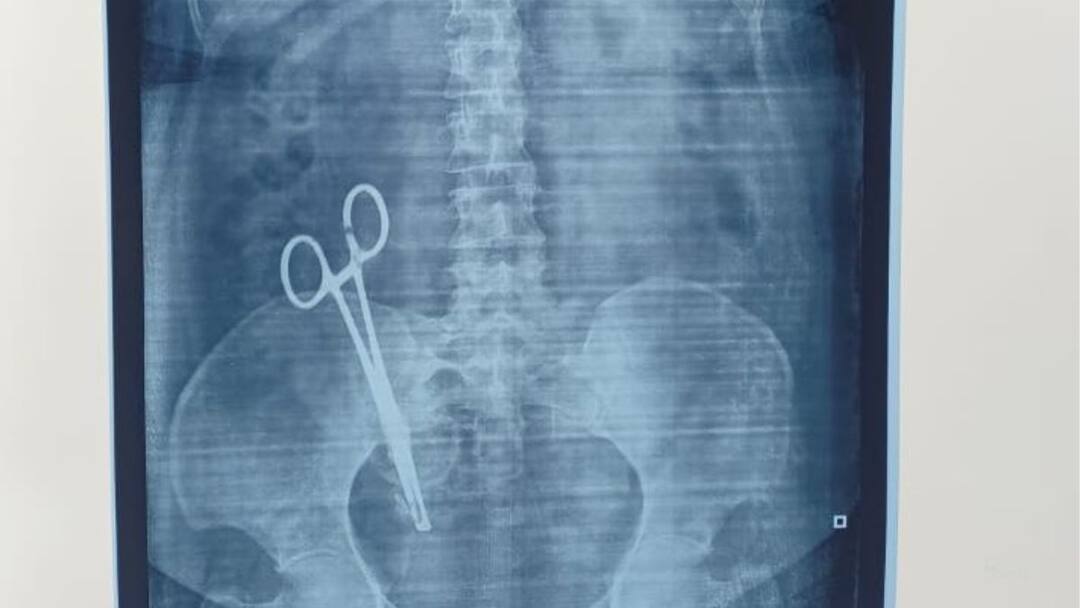

Scissor in Stomach: இப்படி ஒரு டாக்டரா..! உ.பி., மக்கள் ஷாக், 17 வருடங்களாக வயிற்றில் கத்திரிக்கோல்.. 🕑 Sun, 30 Mar 2025

Scissor in Stomach: இப்படி ஒரு டாக்டரா..! உ.பி., மக்கள் ஷாக், 17 வருடங்களாக வயிற்றில் கத்திரிக்கோல்..

Scissors in Stomach: உத்தரபிரதேசத்தில் பெண்ணின் வயிற்றில் 17 வருடங்களாக இருந்த கத்திரிக்கோல் அறுவை சிகிச்சை மூலம் அகற்றப்பட்டுள்ளது. வயிற்றில்